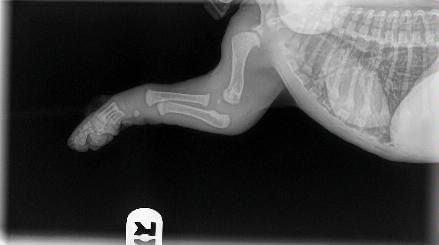

For those of you with young puppies, being aware of how much exercise they are getting per day is extremely important to protect their growing bodies. I know a lot of you will be desperate to take your pups nice long walks as we make the most of the end of summer but too much exercise can be very damaging to puppies’ joint and bone development. The photos below show how much growing still has to be done before a puppies bones are fully grown/formed and connected to the relevant muscles, tendons and ligaments.

It is because of this that we need to limit the exercise puppies do each day in order to ensure their bones and joints grow healthily and are not put under too much stress at a young age. Too much exercise whilst they are still growing could cause a lot of problems later in adulthood if we are not careful.